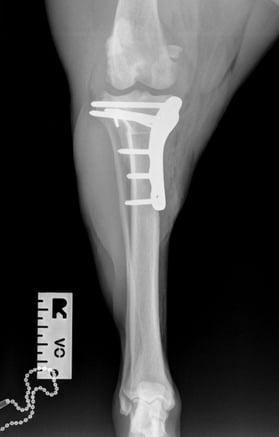

Preoperative measurements indicated a tibial plateau angle (TPA) of 25°. A TPLO saw blade size 24 was used, achieving a rotation of 8.3 mm. Pre-surgical measurements were: A = 11 mm, B = 13 mm, and C = 35 mm.

A 3.5 mm TPLO locking plate was placed with two compression screws. A 2 mm anti-rotational pin was left in situ, as it did not interfere with the placement of the proximal fragment screws.

Postoperative radiographs showed that the proximal screw of the distal fragment is slightly longer than expected, but this is not anticipated to cause clinical issues. GImplants are in good position, there is correct compression and alignment is also optimal.

Postoperative TPA measured at 4.3°.

At the first postoperative recheck (day 3), Luna was nearly fully weight-bearing with only mild lameness. The surgical site showed excellent healing and 6 weeks post-op xrays (Figs. 7 and 8) show good ossification of osteotomy line and good position of implants.

Fig. 7

Fig. 8